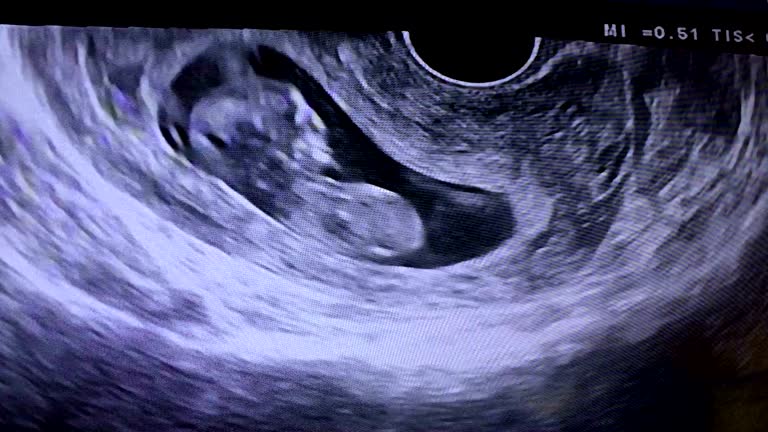

2. 术前检查:根据医生的建议,进行一系列术前检查,如血液检查、超声检查、内分泌检查等,确保手术顺利进行。

3. 胚胎培养:在手术当天,医生会采集卵子和精子,进行体外受精。受精成功后,将胚胎培养至第三天,进行PGS/PGD检测。

4. 胚胎移植:经过检测,选择染色体正常的胚胎进行移植。移植后,患者需按照医嘱进行黄体支持治疗,提高成功率。

5. 术后随访:移植后,患者需定期进行随访,了解胚胎着床情况、妊娠情况等。